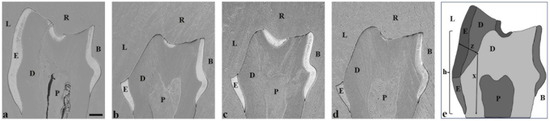

| Negative ctr. | Positive ctr. | Fluoride Varnish | Silver Fluoride Solution | |

|---|---|---|---|---|

| Lingual tooth height (h) | 723 ± 29 | 435 ± 42 | 472 ± 34 | 510 ± 37 * |

| Lingual enamel/dentin loss (z) | - | 136 ± 23 | 129 ± 35 | 88 ± 17 * |